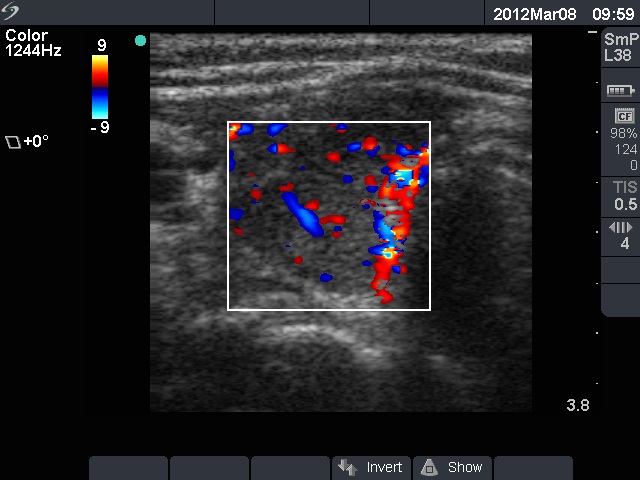

First examination (first row):

Clinical presentation: A 28-year-old woman was referred for evaluation of a recurrent hyperthyroidism. She underwent radioiodine therapy 3 years ago. She did not require replacement therapy and was euthyroid in the previous 30 months. Her original complaints recurred for two months, including 8 kg loss in weight and tachycardia.

Palpation: Both thyroids were enlarged and moderately firm.

Result of blood test: hyperthyroidism (TSH undetectable, FT4 38.6 pM/L).

Ultrasonography: A diffusely hypoechogenic thyroid was found with multiple more hypoechogenic lesions. None of them corresponded to a nodule. The vascularization was increased.Daily 20 mg methimazole was administered and repeat radioiodine therapy was advised after reaching the euthyroid state.